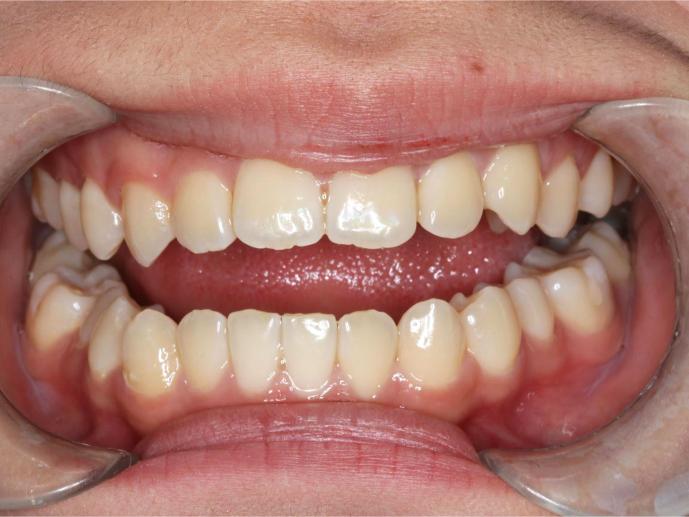

Before and After Images